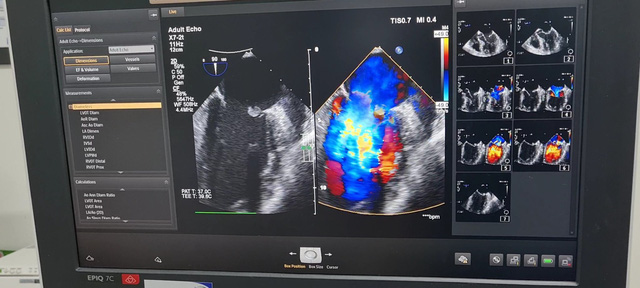

Một trường hợp khác là bệnh nhân N.V. D. (55 tuổi, Hải Phòng), nhập viện trong tình trạng khó thở dữ dội, đau ngực trái kèm sốt cao, suy kiệt, tự điều trị tại nhà không đỡ. Kết quả xét nghiệm cho thấy bệnh nhân bị nhiễm vi khuẩn Streptococcus oralis trong máu. Siêu âm tim cho thấy tình trạng sùi loét thủng 2 van tim. Bác sĩ khoa Hồi sức tim mạch nhanh chóng chẩn đoán đây là trường hợp bị nhiễm trùng máu nặng, nhiễm trùng lan tới cả van tim. Được biết trước đó, bệnh nhân bị đau khớp gối và đau lưng, đã được bác sĩ tư nhân tiêm Corticoid trực tiếp vào khớp gối và cột sống thắt lưng. Mặc dù triệu chứng đau khớp có đỡ, nhưng sau khi tiêm khớp được 2 ngày, bệnh nhân bị sốt triền miên, mệt mỏi và khó thở liên tục.